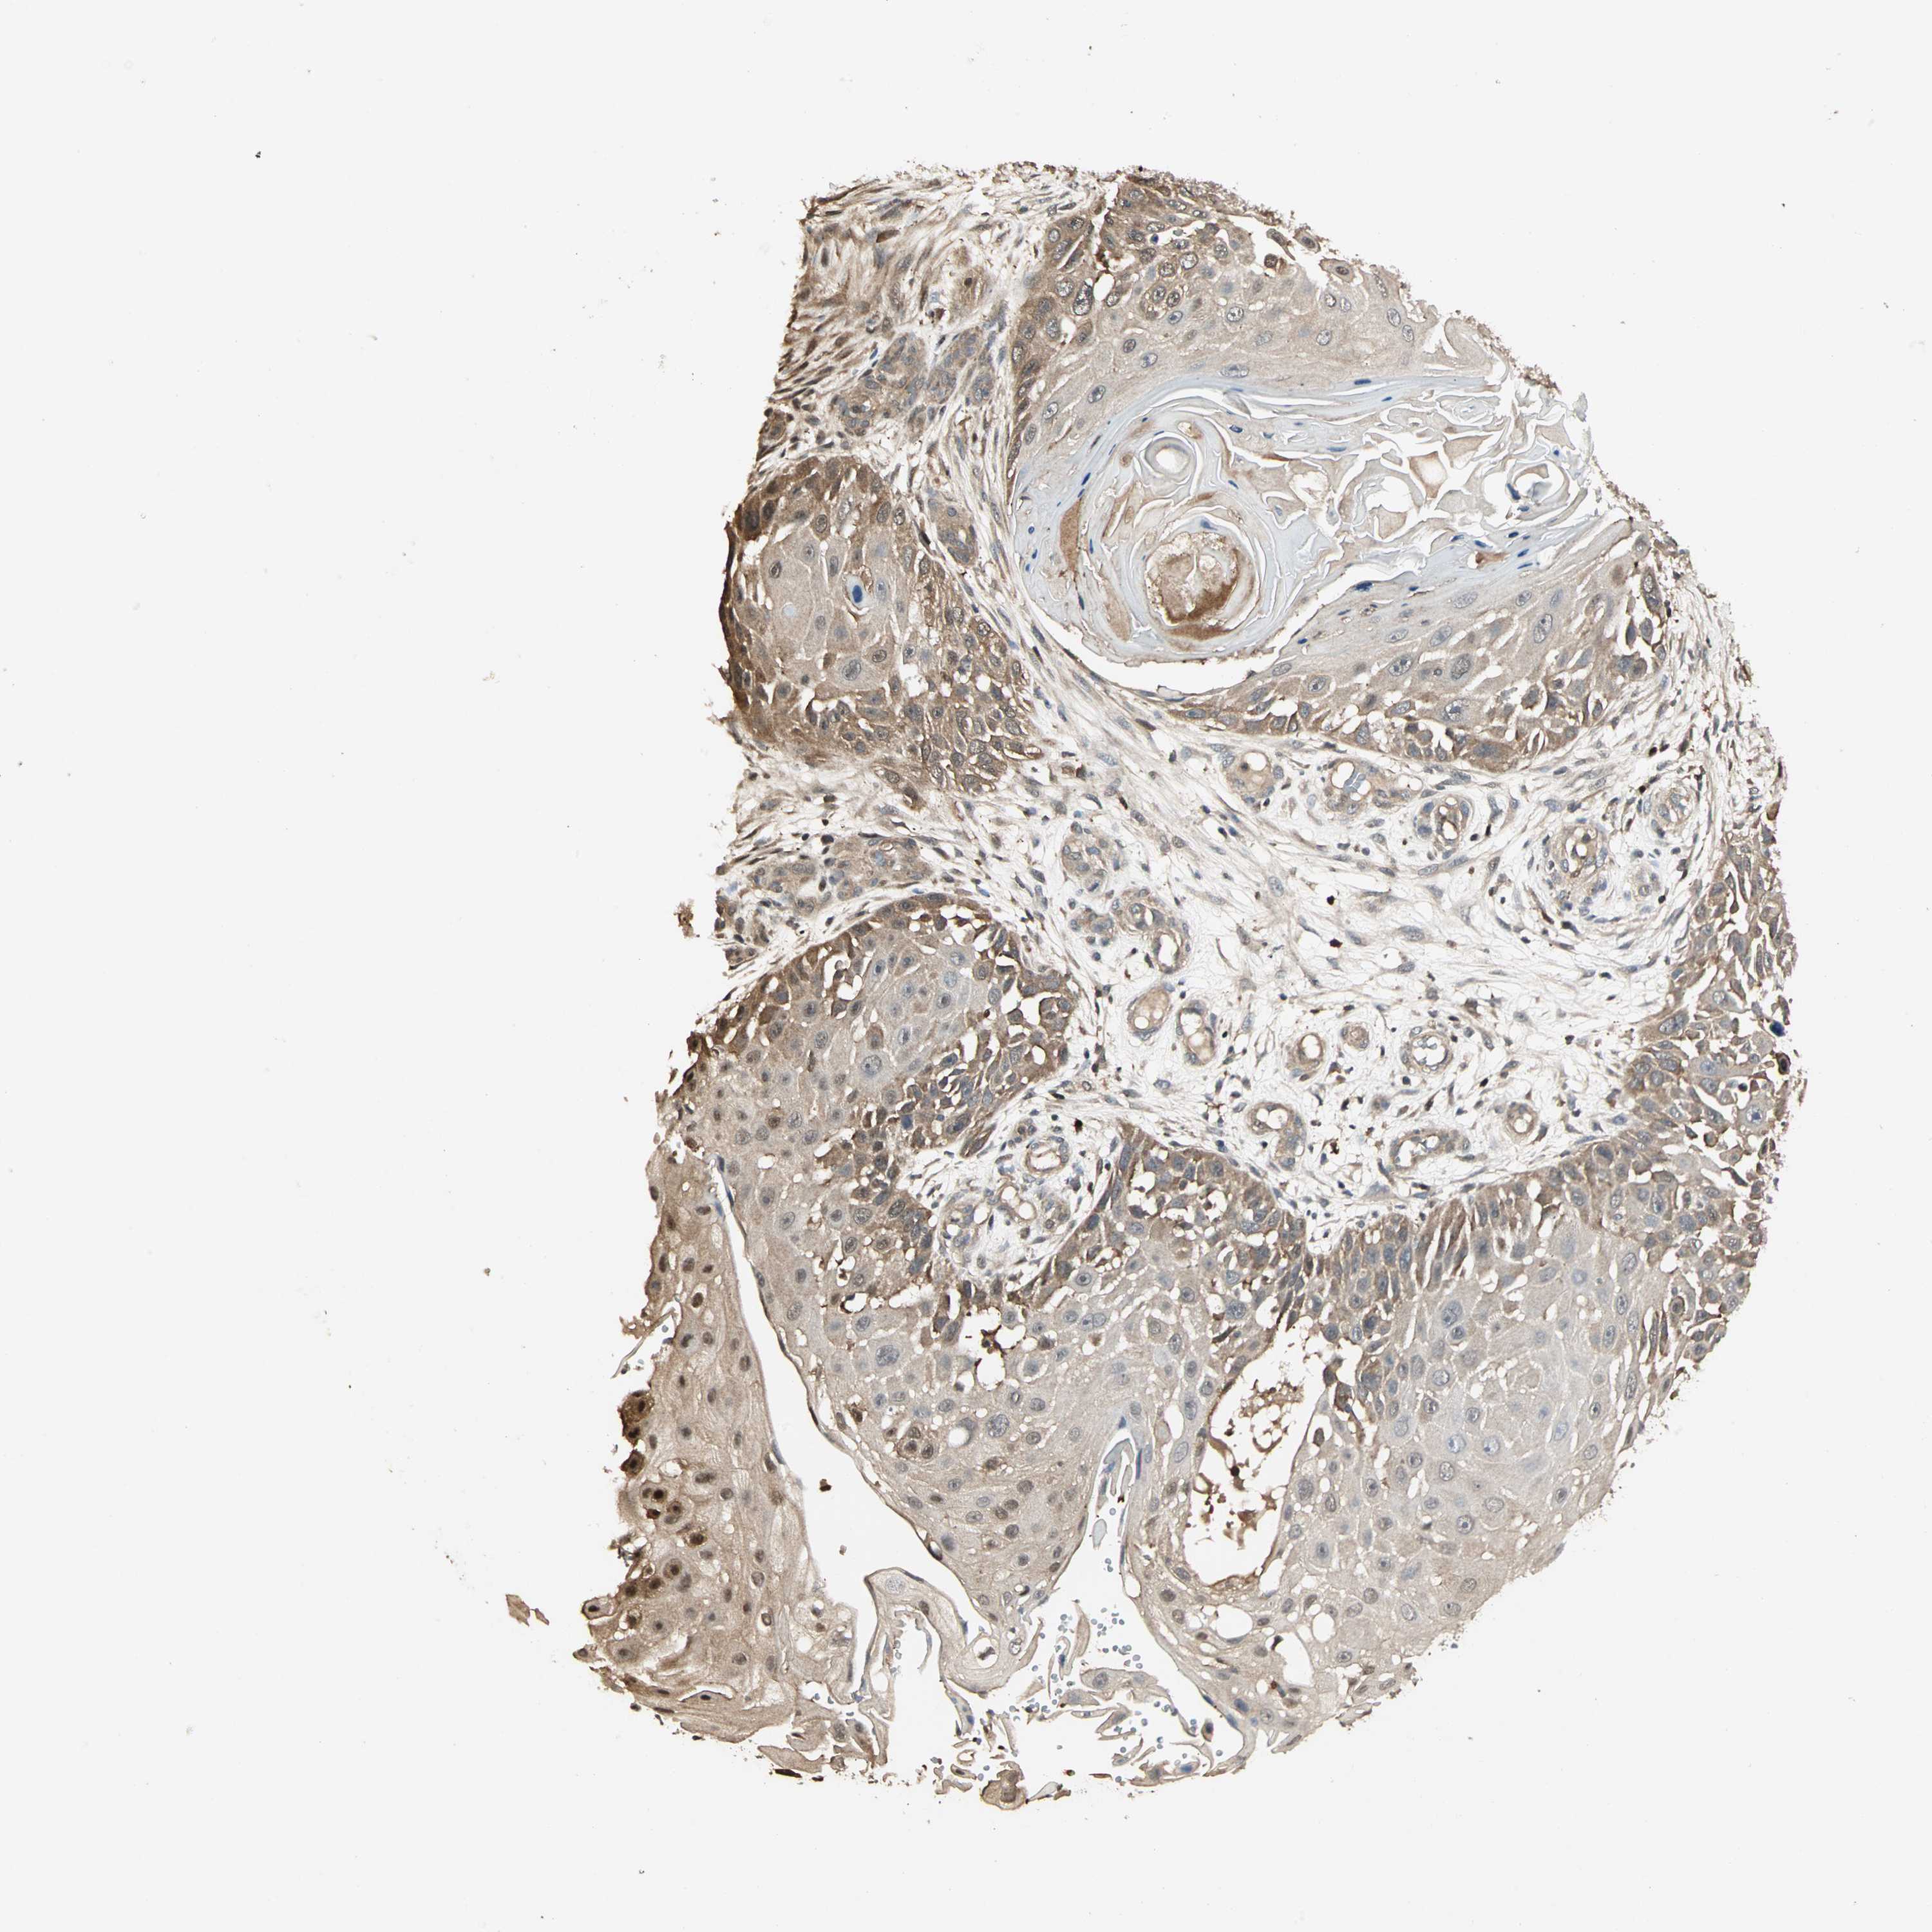

CANCER SKIN CANCER Show tissue menu

Basal cell and squamous cell cancer

SKIN CANCER - Protein expressioni

A mouse-over function shows sample information and annotation data. Click on an image to view it in a full screen mode. Samples can be filtered based on level of antibody staining by selecting one or several of the following categories: high, medium, low and not detected. The assay and annotation is described here.

Each image is clickable and will lead to virtual microscopy that enables deeper exploration of all samples and also displays staining intensity scores, fraction scores and subcellular localization as well as patient and tissue information for each sample.

Antibody HPA007716

Staining

High

Strong

Quantity

>75%

Location

Nuclear

Squamous cell carcinoma, NOS

Squamous cell carcinoma, metastatic, NOS

Basal cell carcinoma

Papilloma, NOS